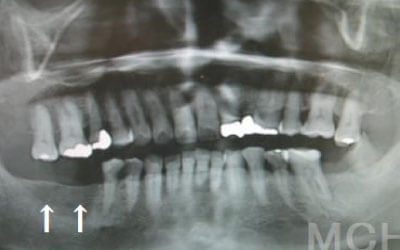

お口の状態や噛み合わせによるので一概には言えないですが、基本的には奥歯がお勧めです。

特に大臼歯と言われる一番奥と奥から二番目の歯の部分です。

噛み合わせの力の60%以上がこの奥から2つの歯で支えているので、ここをしっかりインプラントで治療するのはお勧めです。

Dr.明石

しばらくすると抜けたままでも慣れてきますが、大きな問題が発生します。

1 周囲の歯が早く抜ける

抜けた歯に掛かるはずだった噛むときの力は、気が付かずに別の歯が負担しています。 それにより残っている歯が突然折れて抜歯になることはよくあります。

2 歯が傾いてくる、落ちてくる

歯の位置は互いに支え合ってバランスを保っています。 つまり、歯が抜けることによって支えが無くなり抜けた部分の両隣の歯が倒れたり、 上の歯が下がってきたりします。